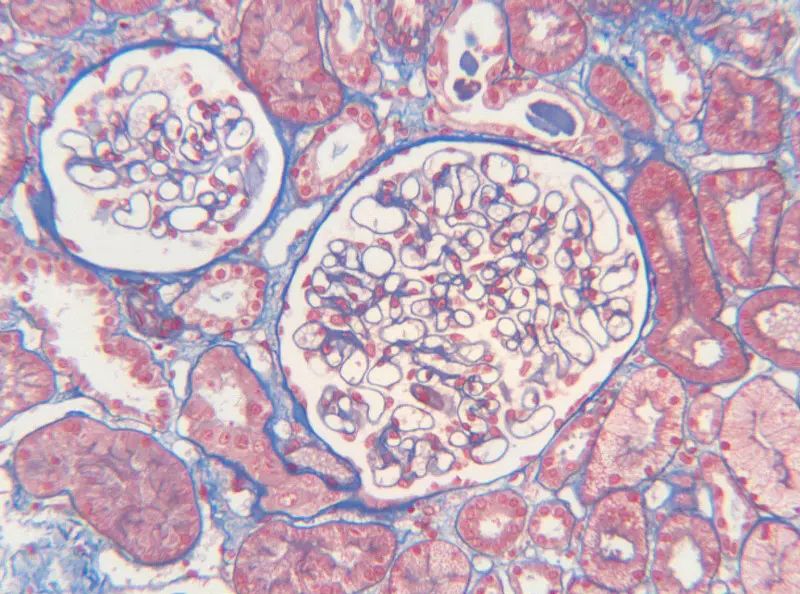

人腎組織

總之,MASSON染色是一種重要的組織學染色方法,通過其獨特的染色原理和步驟,可以實現對組織纖維結構的清晰展示和深入分析。在實際應用中,MASSON染色為醫學研究和臨床診斷提供了有力的支持。